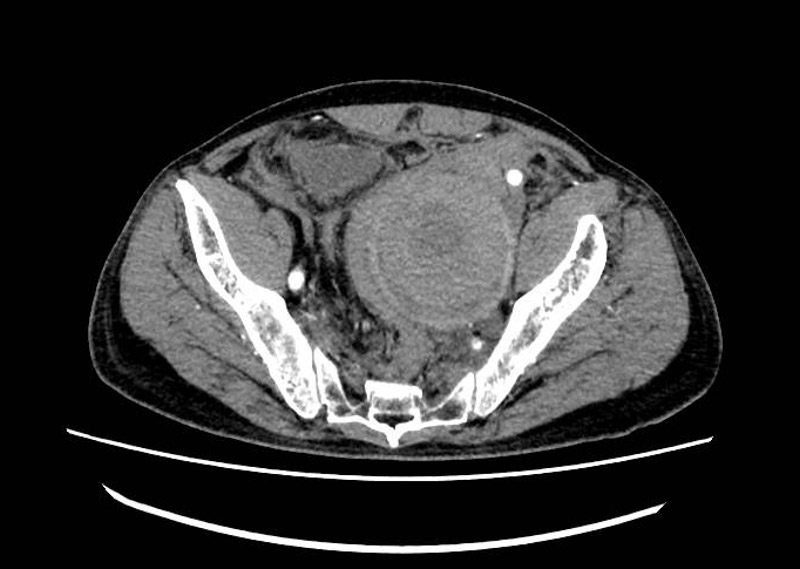

經檢查,醫生發現患者腹膜后、盆腔血腫,左輸尿管擴張、腎積水,考慮左髂內動脈瘤破裂出血。血管外科主任霍鑫博士憑借多年臨床經驗,敏銳地察覺到了危險,認為患者隨時有大出血的可能,需要立即進行介入治療。